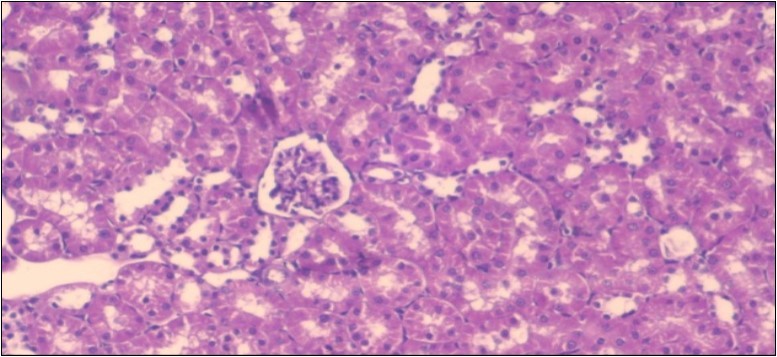

Effect of Ator, Fennel and Their Combination on the Histology of the kidney of the Obese Rats

The histological examination of the kidney of the control rats fed on a standard diet showing normal rounded capsules with normal Bowman's glomeruli, round proximal tubules and elongated distal tubules with high cuboidal cells figure 1. The rats fed (HFD) showed fatty degeneration of the tubules with eosinophilic material deposition, glomerular atrophy with wide urinary space and distal tubules with extrusion of nuclei into lumen figure 2. By comparison kidneys of rats which were treated by fennel after being obese and the control rats observed partial improvement in both Bowman's capsules and proximal tubules. Note the distal tubules show less focal fatty infiltration figure 3.While examination of rats kidney that were treated by ator after obesity showed improvement in Bowman's capsules with normal glomerular and partial improvement in proximal tubules and distal tubules, figure 4. Kidney of rats that were treated by fennel and ator after obesity and the control rats showed high improvement in the tissues with normal glomerular and that Most of Bowman's capsules and renal tubules, restoring their normal appearance figure 5.

Figure 5.Photomicrograph of kidney section of treated rat with both fennel herb and Ator drug showing highly improved tissue with normal glomerular. Note, most Bowman's capsules and renal tubules, restoring their normal appearance (star). (H&E) (40X).